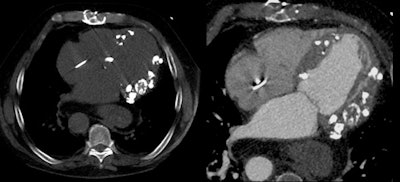

For example, a patient with end-stage renal disease had secondary hyperparathyroidism due to lack of compliance with medication or dietary restrictions; radiography showed extensive calcifications in the bones of the hand, with corresponding changes visible in the heart where extensive calcifications in the myocardium were associated with extensive pericardial effusion.

In a recent case from Stanford, myocardial calcifications were an incidental finding in a patient scheduled for aortic valve replacement.

"Unfortunately, I cannot provide a final diagnosis as to why the patient has so much calcium in the myocardium, but know it is certainly not secondary hyperparathoroidism because the creatinine was normal," Becker said. "My assumption is that this is of infectious origin."

Patient scheduled for aortic valve replacement was found to have significant calcification in the myocardium of unknown etiology.Another incidental finding occurred in a patient being readied for a transcatheter aortic valve replacement (TAVR). However, instead of aortic disease he was found to have hypertrophic obstructive cardiomyopathy. CT is very helpful because this disease requires a very morphologic diagnosis, in this case showing a mass of soft tissue in the myocardium in the territory of the aortic outflow track as an indicator of hypertrophic obstructive cardiomyopathy.